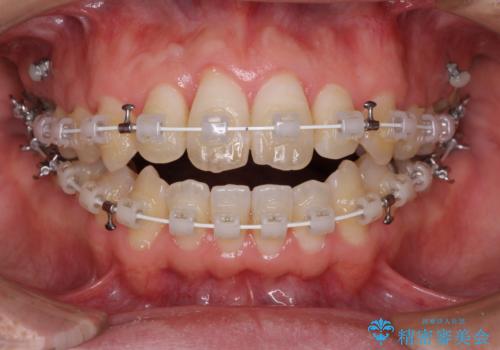

- 矯正装置

- 審美装置

上顎奥歯付近にアンカースクリューを用い、上顎歯列全体の後方移動と、大臼歯圧下を促し、前歯の上下関係を改善することとしました。

奥歯には目立つ銀歯が多くあるので、矯正治療後には下顎の銀歯をセラミッククラウンやセラミックインレーにより、補綴・修復治療することとしました。